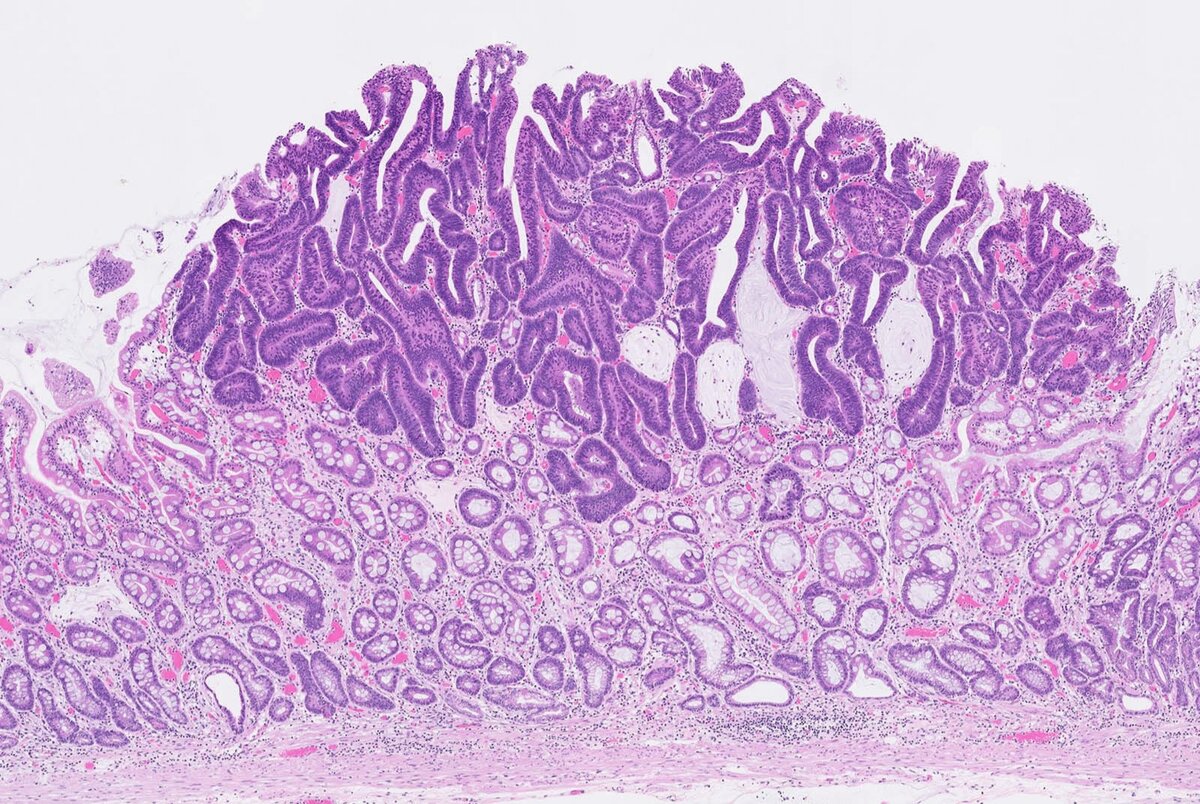

Таким же образом ординатор может знать, что «гиперхроматический» или «атипичный» — это прилагательные, означающие свойства злокачественных клеток. Тем не менее, нужно увидеть огромное количество примеров того, что эксперты называют атипичным, чтобы действительно понять, какие качества клетки эти прилагательные означают. Поэтому чем больше стёкол вы просмотрите, тем опытнее будет ваш глаз. Ни одна книга не может вас этому научить.